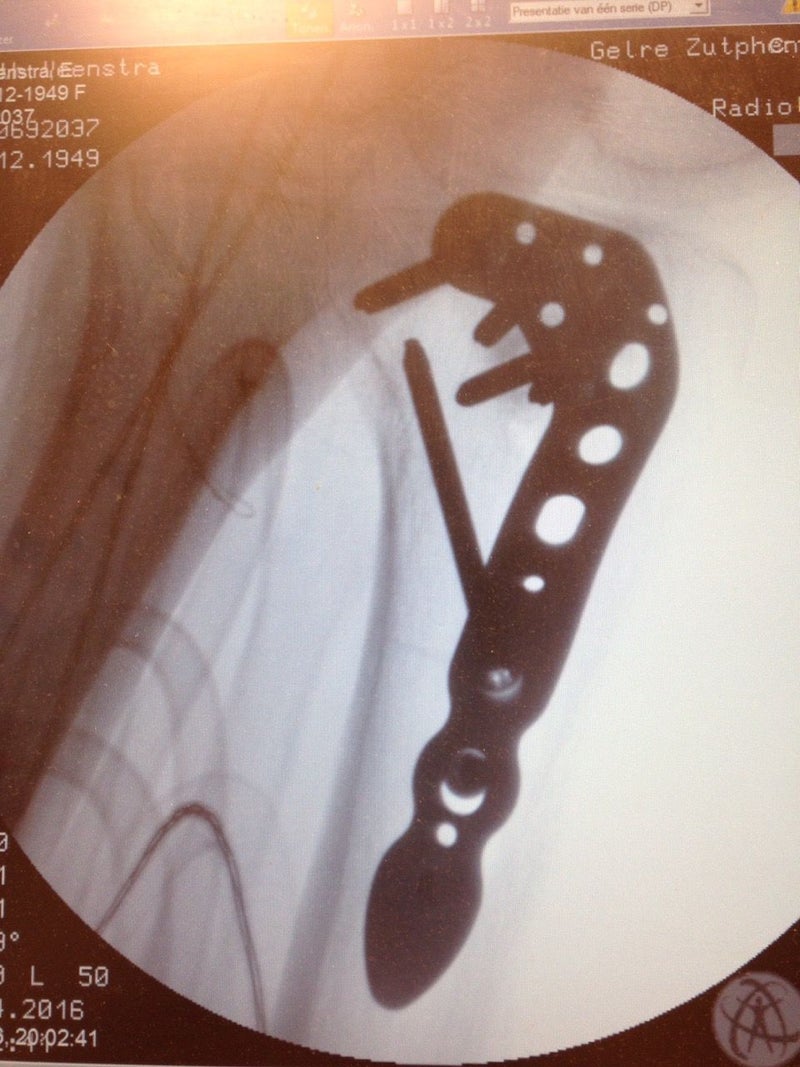

De fysiotherapeut wilde kopieën hebben van de röntgen foto’s om te zien waar de plaat en de schroeven zitten zodat hij t.z.t. eventuele bewegingsbelemmeringen bij de therapie kan verklaren. Natuurlijk wilden wij ook de foto’s ook zien om goed te begrijpen wat de operatie behelsd heeft.

linkerzijkant knie met het plaatje

Everdien begrijpt nu ook waarom ze op bepaalde plaatsen bot pijn heeft. Er zitten immers meerdere schroeven door het bot heen. Ze gebruikt nu 3 paracetamol per dag.